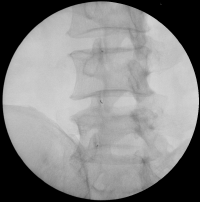

척추 후관절 치료술 (Facet joint block)

– 척추후관절을 담당하는 신경을 치료하는 방법.

척추후관절은 척추의 움직임을 안내하고 제한하는 역할을 하는데 내측지차단술을 시행함으로써 후관절을 부드럽게 만들어 척추의 움직임을 원할하게 해주며 통증을 가라 앉힌다.

내측지차단술(Medial Branch Block)

– 척추 관절로 가는 신경을 치료하는 방법.

척추 후 관절은 위쪽과 아래쪽 두 갈래의 척추신경으로부터 신경지배를 받고 있습니다. 그래서 두 군데의 신경을 치료해야 합니다. 이 방법은 통증을 일으키는 부위가 확실치 않을 때 그 부위를 찾는 방법으로 활용되기도 합니다.

치료 방법

컴퓨터 영상 장치를 보면서 통증을 일으키는 관절에 바늘을 삽입하여 주사 약물을

주입합니다.

(치료 후 경우에 따라 해당 부위의 일시적인 통증, 발적, 부종 등이 있을 수 있습니다.)